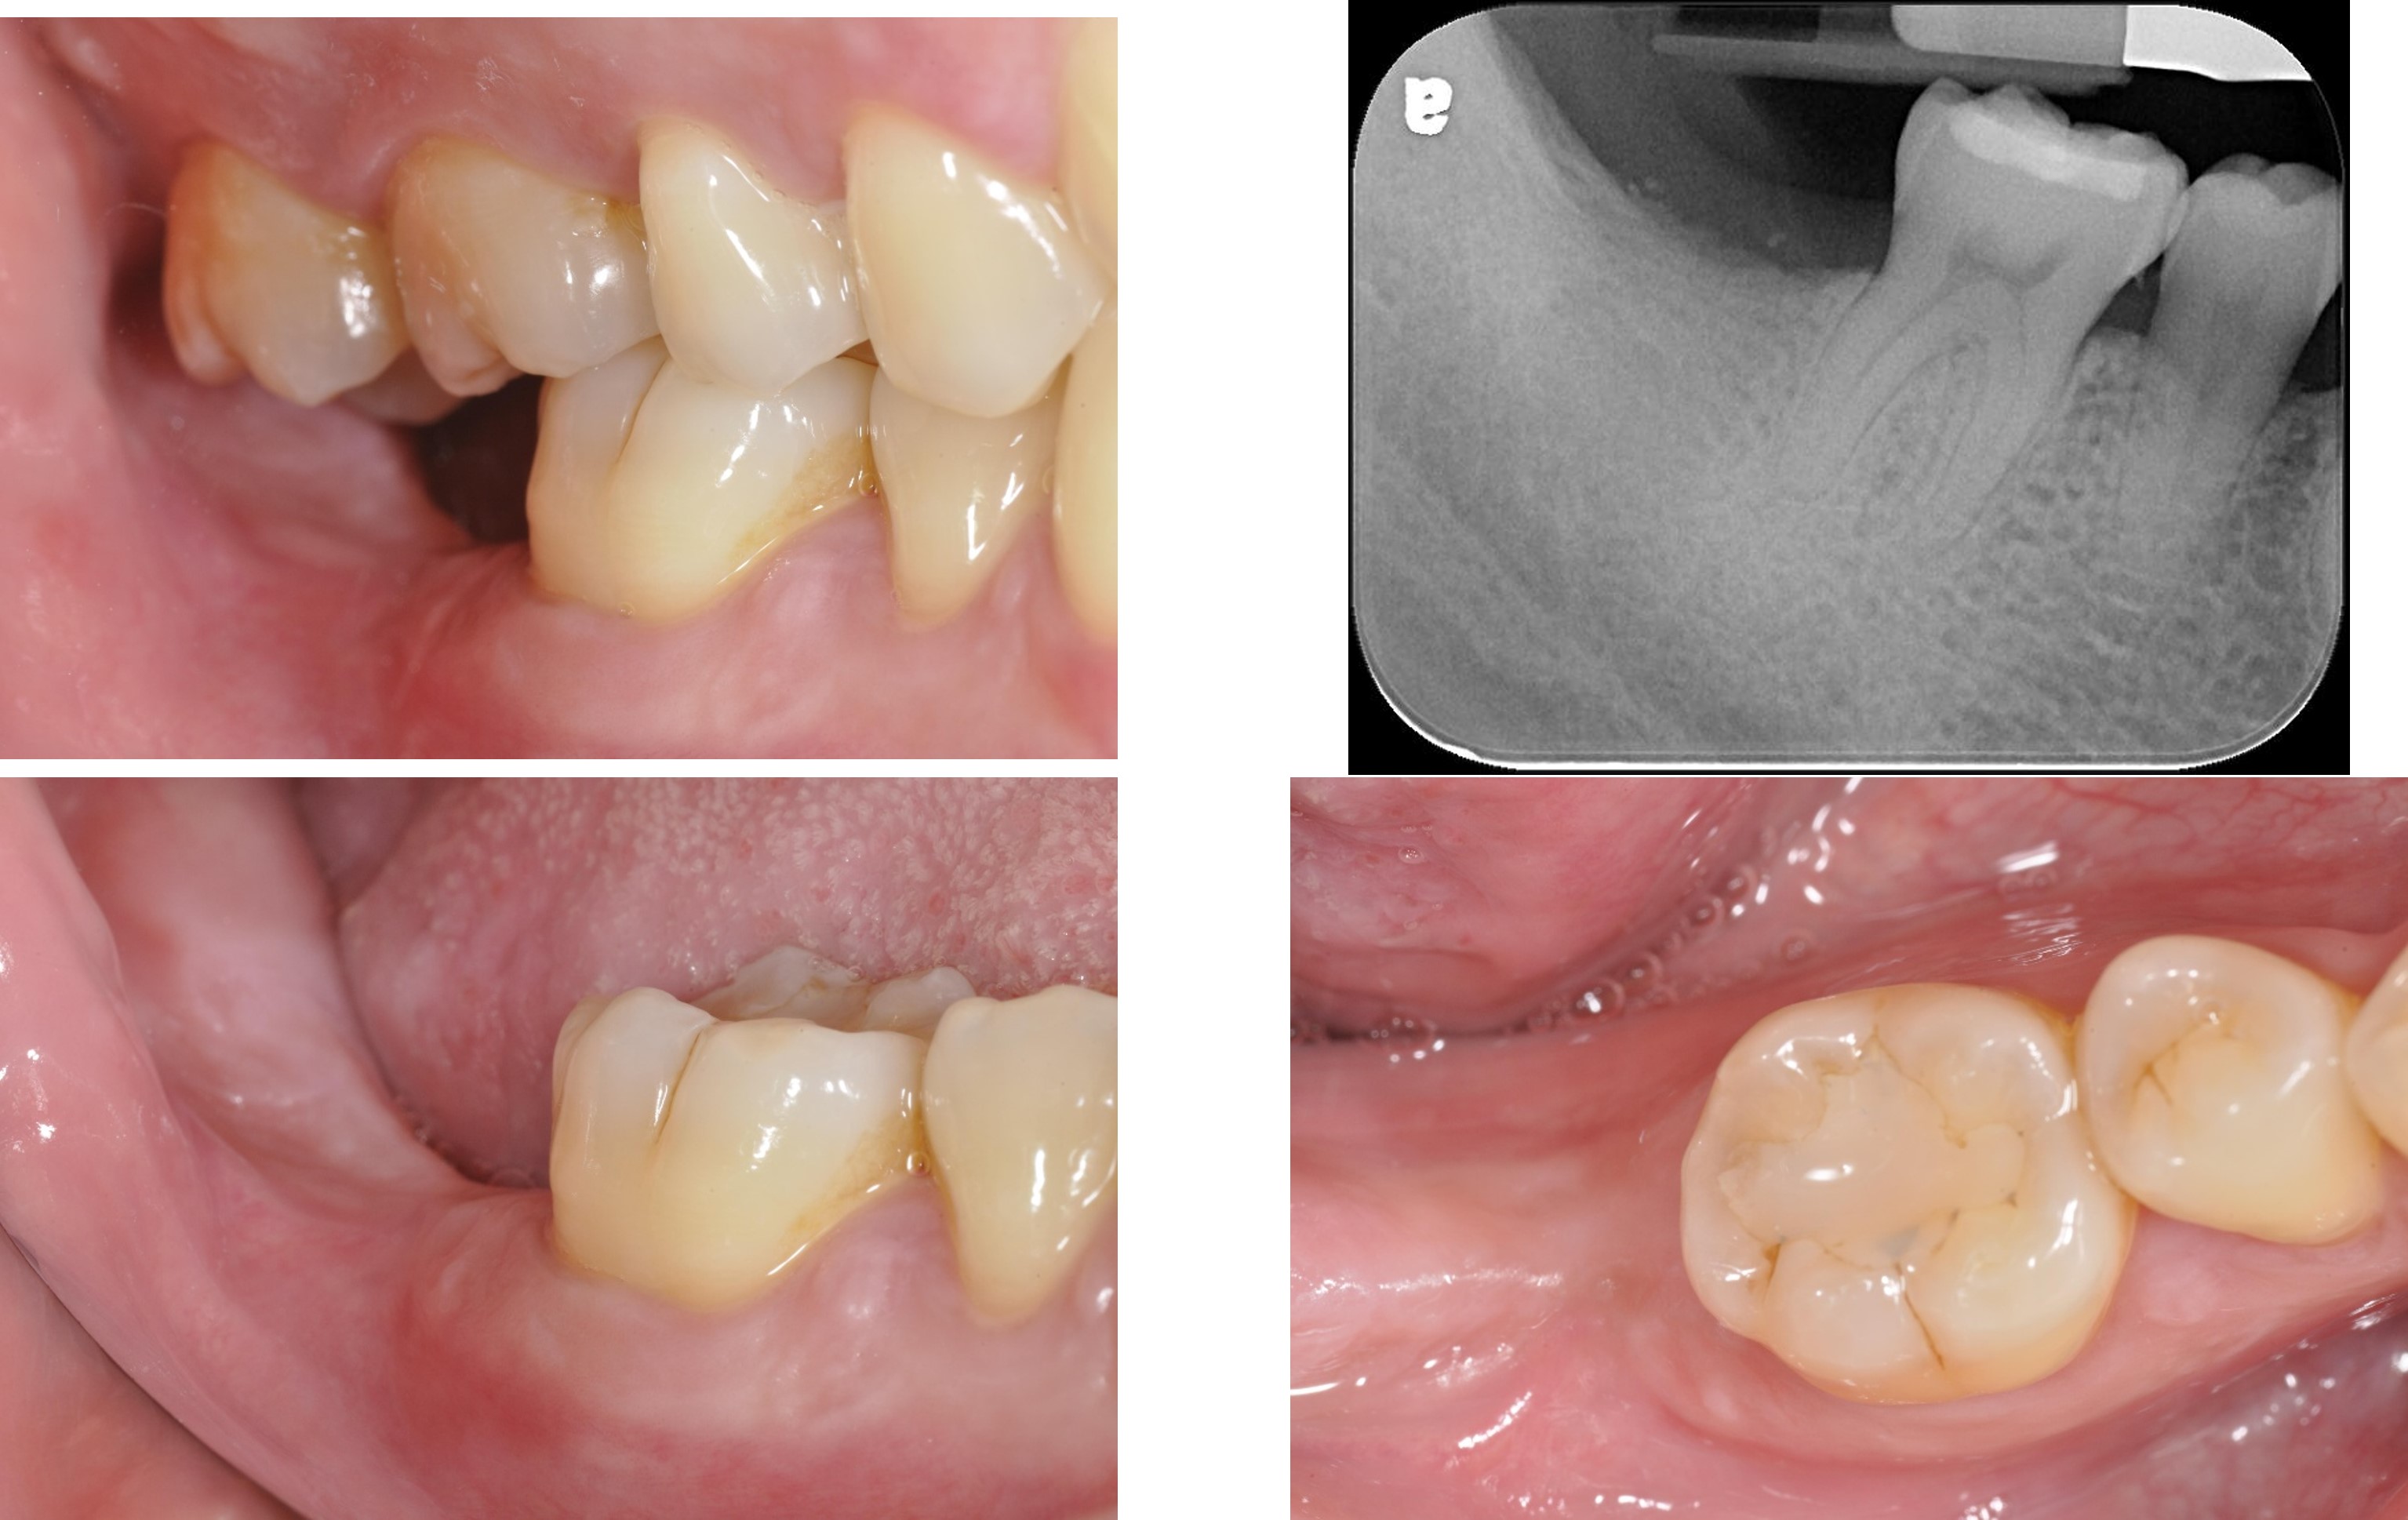

治療後,咬合牙周適應良好

治療後,密合度良好

術前、術後比較